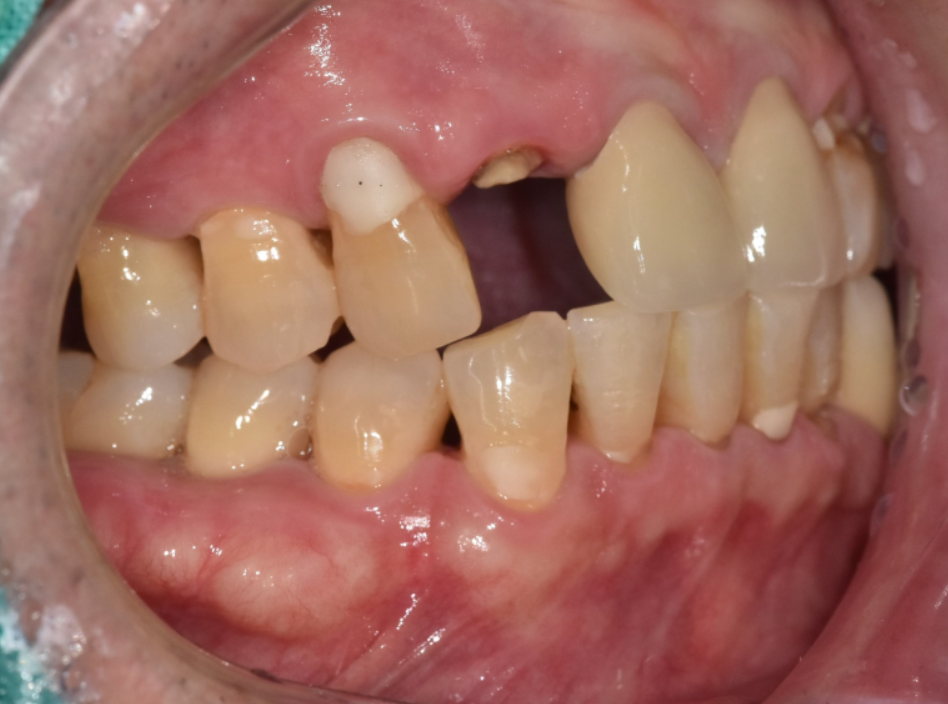

240831 뿌리만 남은 앞니

240831

250828

위의 3가지 경우에 해당하면 안타깝지만 발치 후 임플란트를 고려해야 됩니다.